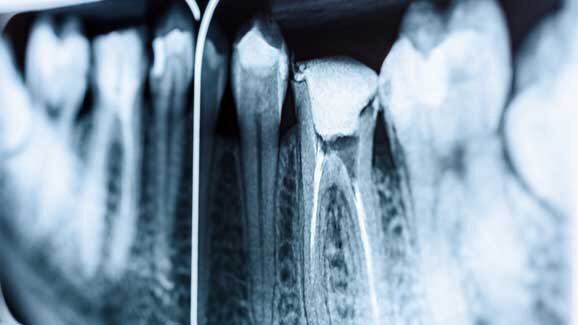

Според зъболекаря пациентът е бил под непрекъснатото наблюдение на опитен анестезиолог по време на 8-часовата операция, която включвала лечение на кореновите канали и поставяне на множество обтурации. По информация от немския портал bild.de младият мъж е изпитвал неимоверен страх от зъболекари и е поискал обща упойка. Операцията е включвала лечение на четири коренови канала, поставяне на шест корони и 24 обтурации.

Първоначалната аутопсия установила, че младежът е страдал от сърдечнoсъдови проблеми и причината за смъртта му е сърдечна недостатъчност. В интервю за немската медия зъболекарят обяснява, че денталните процедури са протекли без никакви усложнения въпреки сравнително необичайната употреба на обща упойка.